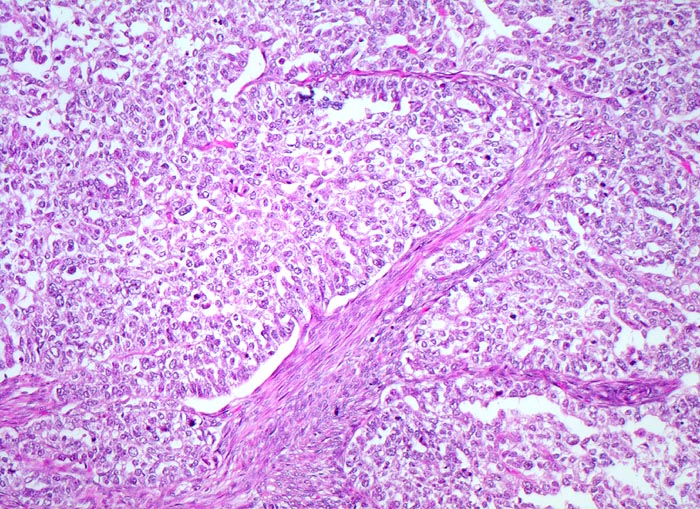

Endometrioide Karzinome bestehen aus tubulären Drüsen, welche von einem mehrreihigen Epithel ausgekleidet werden. Schleim ist meist nicht oder nur apikal in den Zellen vorhanden. Die Ausdehnung der soliden Areale und die zytologischen Atypien bestimmen den Differenzierungsgrad (low-grade versus high-grade). Metaplastisches Plattenepithel findet sich häufig in endometrioiden Karzinomen und hilft bei der Abgrenzung von anderen Subtypen. Das endometrioide Karzinom kann sich innerhalb von Adenomyoseherden im Myometrium entwickeln (> 4482). In diesen Fällen kann die Bestimmung der Infiltrationstiefe erschwert sein.

• Anstelle des Endometriums findet sich in der linken Hälfte des Uteruskavums ein Adenokarzinom bestehend aus architektonisch komplexen Drüsen. Die Drüsen liegen teils dos à dos ohne erkennbares Stroma zwischen zwei Drüsenschläuchen.

• Tumorzellverbände infiltrieren die glatte Muskulatur des Myometriums.

• Tumordrüsen ausgekleidet von mehrreihig angeordneten Tumorzellen mit hyperchromatischen polymorphen längsovalen Tumorzellkernen mit zahlreichen Mitosen. Die Morphologie der Tumordrüsen erinnert an proliferatives Endometrium.